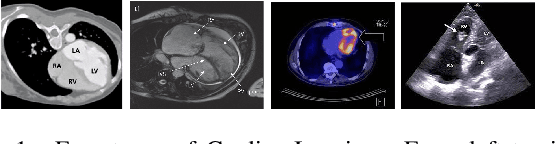

Abstract:Unsupervised domain adaptation approaches have recently succeeded in various medical image segmentation tasks. The reported works often tackle the domain shift problem by aligning the domain-invariant features and minimizing the domain-specific discrepancies. That strategy works well when the difference between a specific domain and between different domains is slight. However, the generalization ability of these models on diverse imaging modalities remains a significant challenge. This paper introduces UDA-VAE++, an unsupervised domain adaptation framework for cardiac segmentation with a compact loss function lower bound. To estimate this new lower bound, we develop a novel Structure Mutual Information Estimation (SMIE) block with a global estimator, a local estimator, and a prior information matching estimator to maximize the mutual information between the reconstruction and segmentation tasks. Specifically, we design a novel sequential reparameterization scheme that enables information flow and variance correction from the low-resolution latent space to the high-resolution latent space. Comprehensive experiments on benchmark cardiac segmentation datasets demonstrate that our model outperforms previous state-of-the-art qualitatively and quantitatively. The code is available at https://github.com/LOUEY233/Toward-Mutual-Information}{https://github.com/LOUEY233/Toward-Mutual-Information